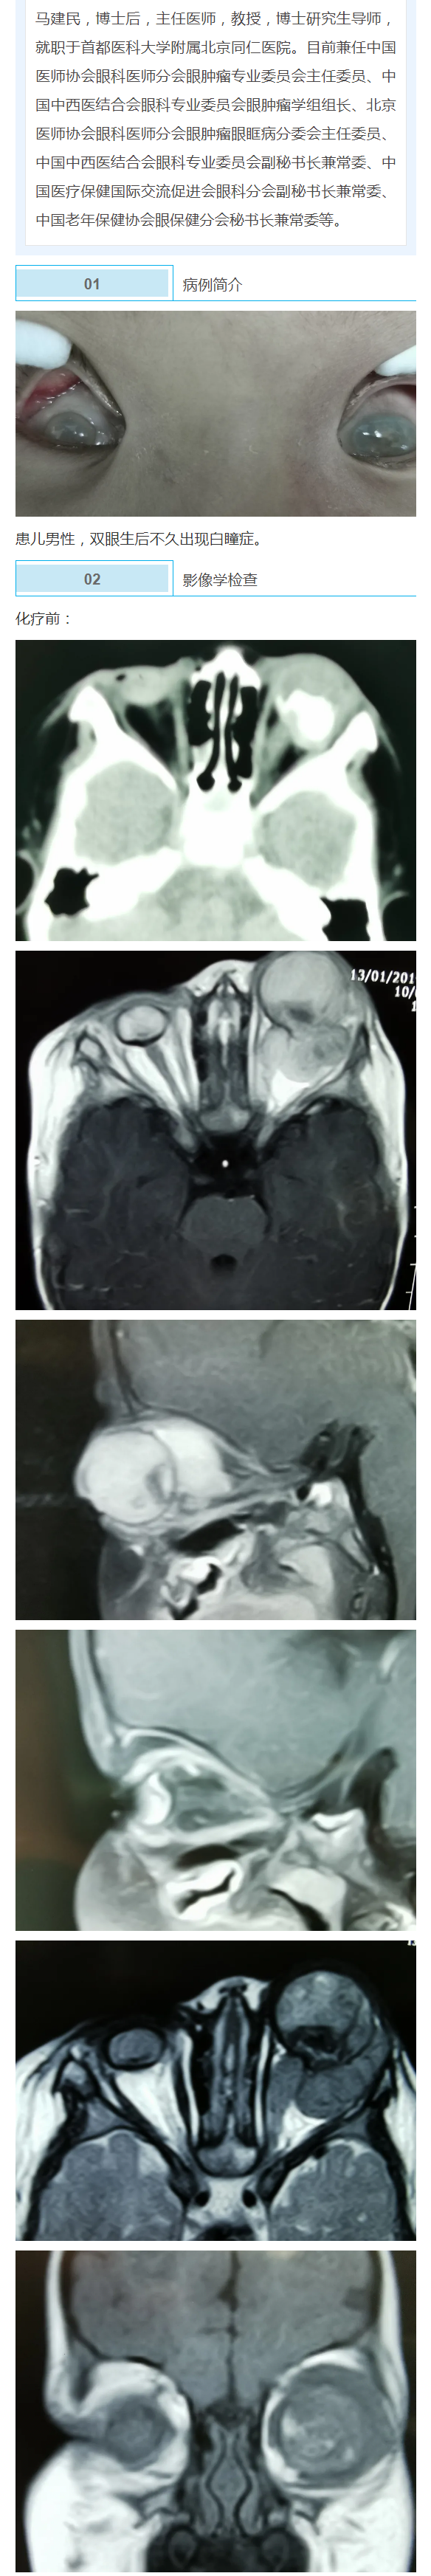

马建民丨眼肿瘤眼眶病图片集锦(198):视网膜母细胞瘤